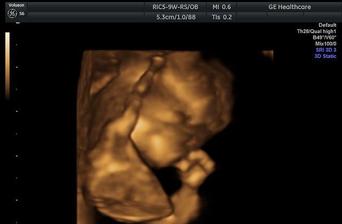

Ivan + Eva = Evan

Naše prvé dieťatko, ktoré sa nám narodilo 11 rokov od našej prvej pusy 🙂 Usmievavý, čarovný chlapček, ktorého meno vzniklo spojením našich dvoch mien. Náš Evčo <3